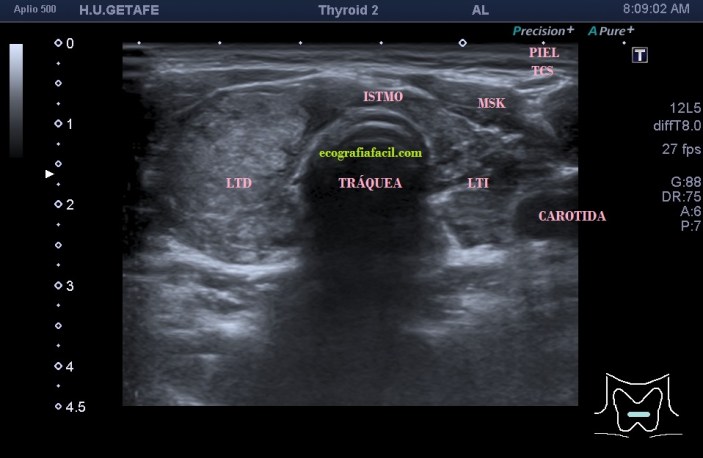

Te enseño las imágenes, típicas de una exploración tiroidea de protocolo con semiología de tiroiditis.

De la imagen 1 a 7 el protocolo habitual, el estudio particular del nódulo con medidas y aplicación del doppler demuestra el aspecto típico del Caballero Blanco.